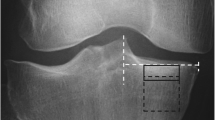

To derive BMD, grayscale Hounsfield units (HU) were converted to equivalent volumetric BMD (mg/cm3 K2HPO4) using subject-specific linear regression equations developed from known densities ranging from − 50 to 375 mg/cm3 K2HPO4 within the QCT phantom included in each individual axial image (r 2 > 0.99) [28] and interpolation to determine equivalent volumetric BMD values. Higher density values were linearly extrapolated (Fig. 1a). Subject-specific half maximum height thresholds [29] were then determined to define the proximal tibial subchondral and cortical surfaces. Two 3D image volumes were built, one including the entire proximal tibia as previously described [13, 28] and another by segmenting individual serial images using semi-automatic region growing and manual correction at the epiphyseal line (Fig. 1b). Both sets of imaged volumes were segmented using commercial software (Analyze10.0; Mayo Foundation, Rochester, MN, USA) and an interactive touch-screen tablet (Cintiq 21UX; Wacom, Krefeld, Germany). Imaged volumes were reoriented to a neutral position where medial and lateral plateaus were approximately parallel. We then divided the imaged volumes into medial and lateral compartments, measured by using 40% of the maximum medial-lateral axis of each respective side [16] (Fig. 1c).

Methodological process consists of converting computed tomography (CT) grayscale intensities to bone mineral density (BMD) using a quantitative CT (QCT) reference phantom (a), followed by building two imaged volumes for each tibia, one with manual correction at the epiphyseal line and one using the full tibia (b). Imaged volumes were divided into lateral and medial regions (c) and then the outer 2.5-mm and subchondral 7.5-mm depth were removed from each imaged volume (d). BMD measurements included epiphyseal BMD between the epiphyseal line and 7.5 mm from the subchondral surface and metaphyseal BMD 10 mm distal from the epiphyseal line (e)

To ensure that trabecular BMD measurements did not include cysts (which would lead to arbitrarily low measures of BMD) [13, 30] or peripheral high-density cortical bone, the most proximal 7.5-mm region (relative to the subchondral surface) was removed from the segmentations (Fig. 1d), as was 2.5 mm of peripheral cortical bone (Fig. 1d). The 7.5-mm depth was based upon observed cyst locations from our earlier work [13, 30] and work by Chiba et al. [31], which limited depth analyses to 5 mm from the subchondral surface. In extreme cases, large cysts extended from the subchondral cortical region (0 − 2.5 mm) through the subchondral trabecular region (2.5–5 mm) and occasionally into depths greater than 5 mm from the subchondral surface. By using a conservative 7.5-mm depth from the subchondral surface, we ensured the exclusion of large cysts from our analysis. Following material removal, we measured epiphyseal trabecular BMD from the 7.5-mm depth to the epiphyseal line (Fig. 1e), which was located approximately 15 mm from the subchondral surface. Metaphyseal trabecular BMD was measured 10 mm distal to the epiphyseal line (Fig. 1e).